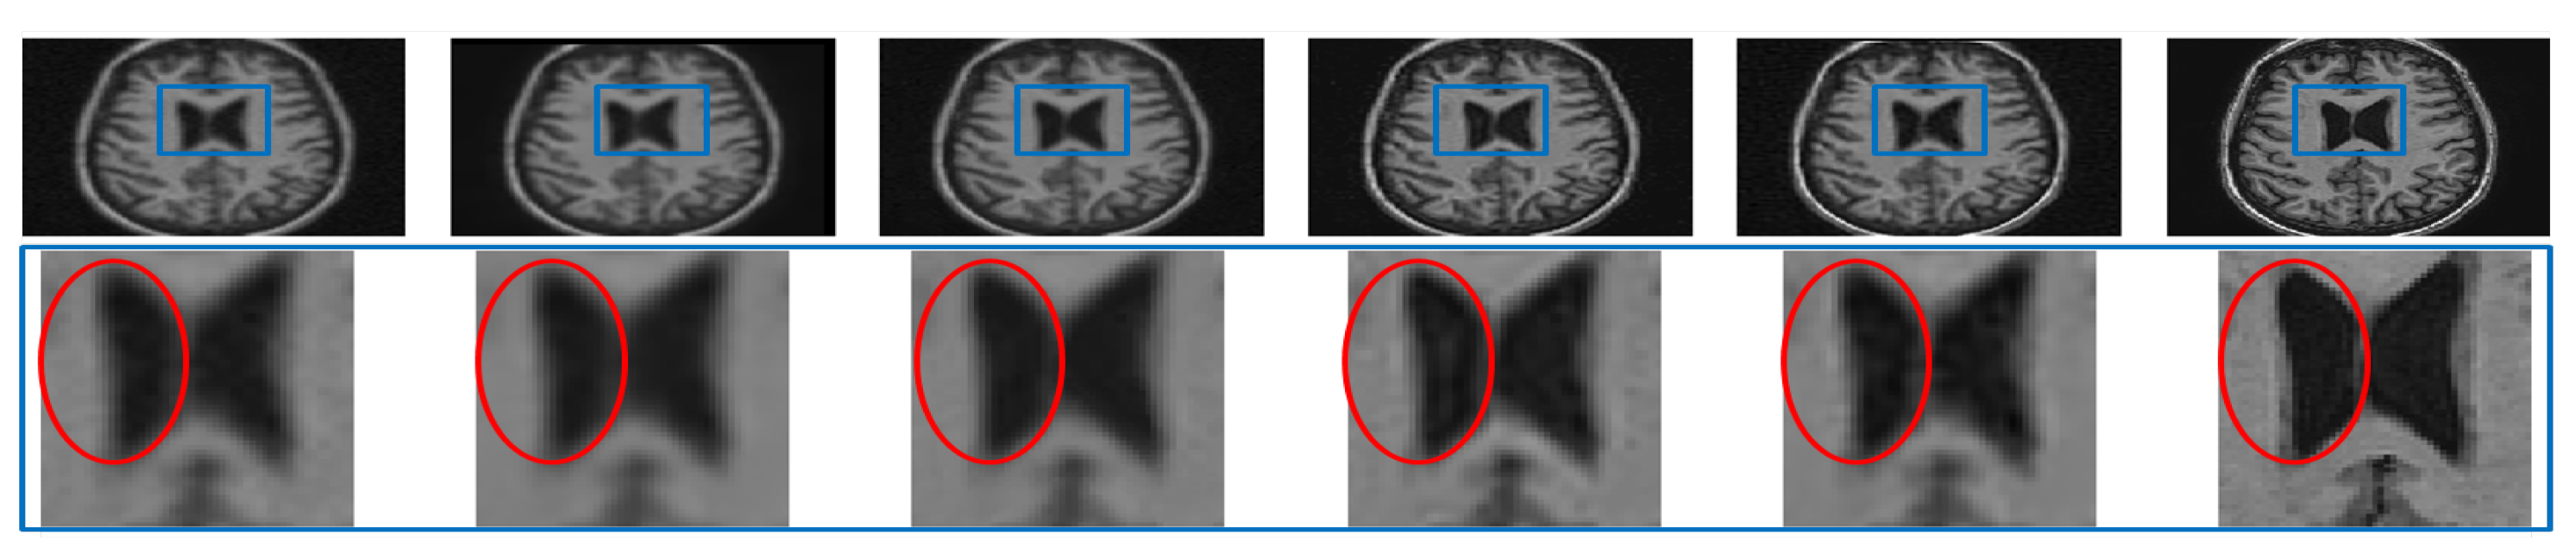

Analysis for Alzheimer Subjects

The clinical applications of the proposed approach can be valid only if no artifacts are introduced while denoising or super resolving. To experimentally verify this, a noisy LR image of an Alzheimer’s subject is restored by different algorithms and compared in the first row of Figure 15. The zoomed version of the region in the blue rectangle (highlighted in the first row) is shown in the second row. It can be observed that interpolated images and NLM3D [13] provide blurred image details. The LRTV [12] approach highlights the CSF flow artifact significantly (which is not as present in the noise-free HR image), may compromise the detection of pathology in the ventricular system, thus compromising the diagnostic capability. The image reconstructed by the proposed approach looks relatively noisy but clearer than existing methods and does not highlight any such artifact; hence, it can aid in accurate diagnosis. The same values of , , and were used to process the MR images of an Alzheimer’s subject obtained from dataset-III as for processing dataset-II and dataset-I. It indicates the generalization of the proposed approach that uses the same values of parameters for different datasets.

Figure 15.

Illustration of super resolving the real MR images of an Alzheimer’s subject degraded with downsampling factor 2 and 2% noise. From Left: Interpolated noisy LR image, spline interpolation of denoised image, NLM3D-based super-resolved denoised image, LRTV-based super resolution of the denoised image, the proposed approach super resolving the noisy LR image, and the original noiseless HR image.